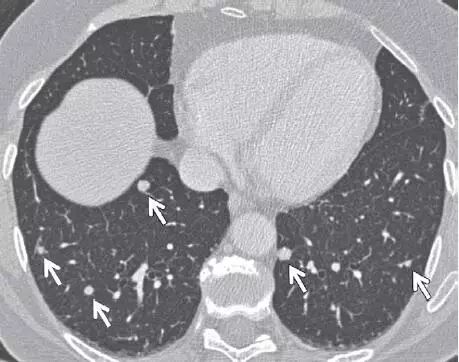

8、转移性结节

图片

图 8 CT 图像,显示继发于转移性甲状腺癌,以下肺分布为主的多个不同大小实性结节(箭头)。